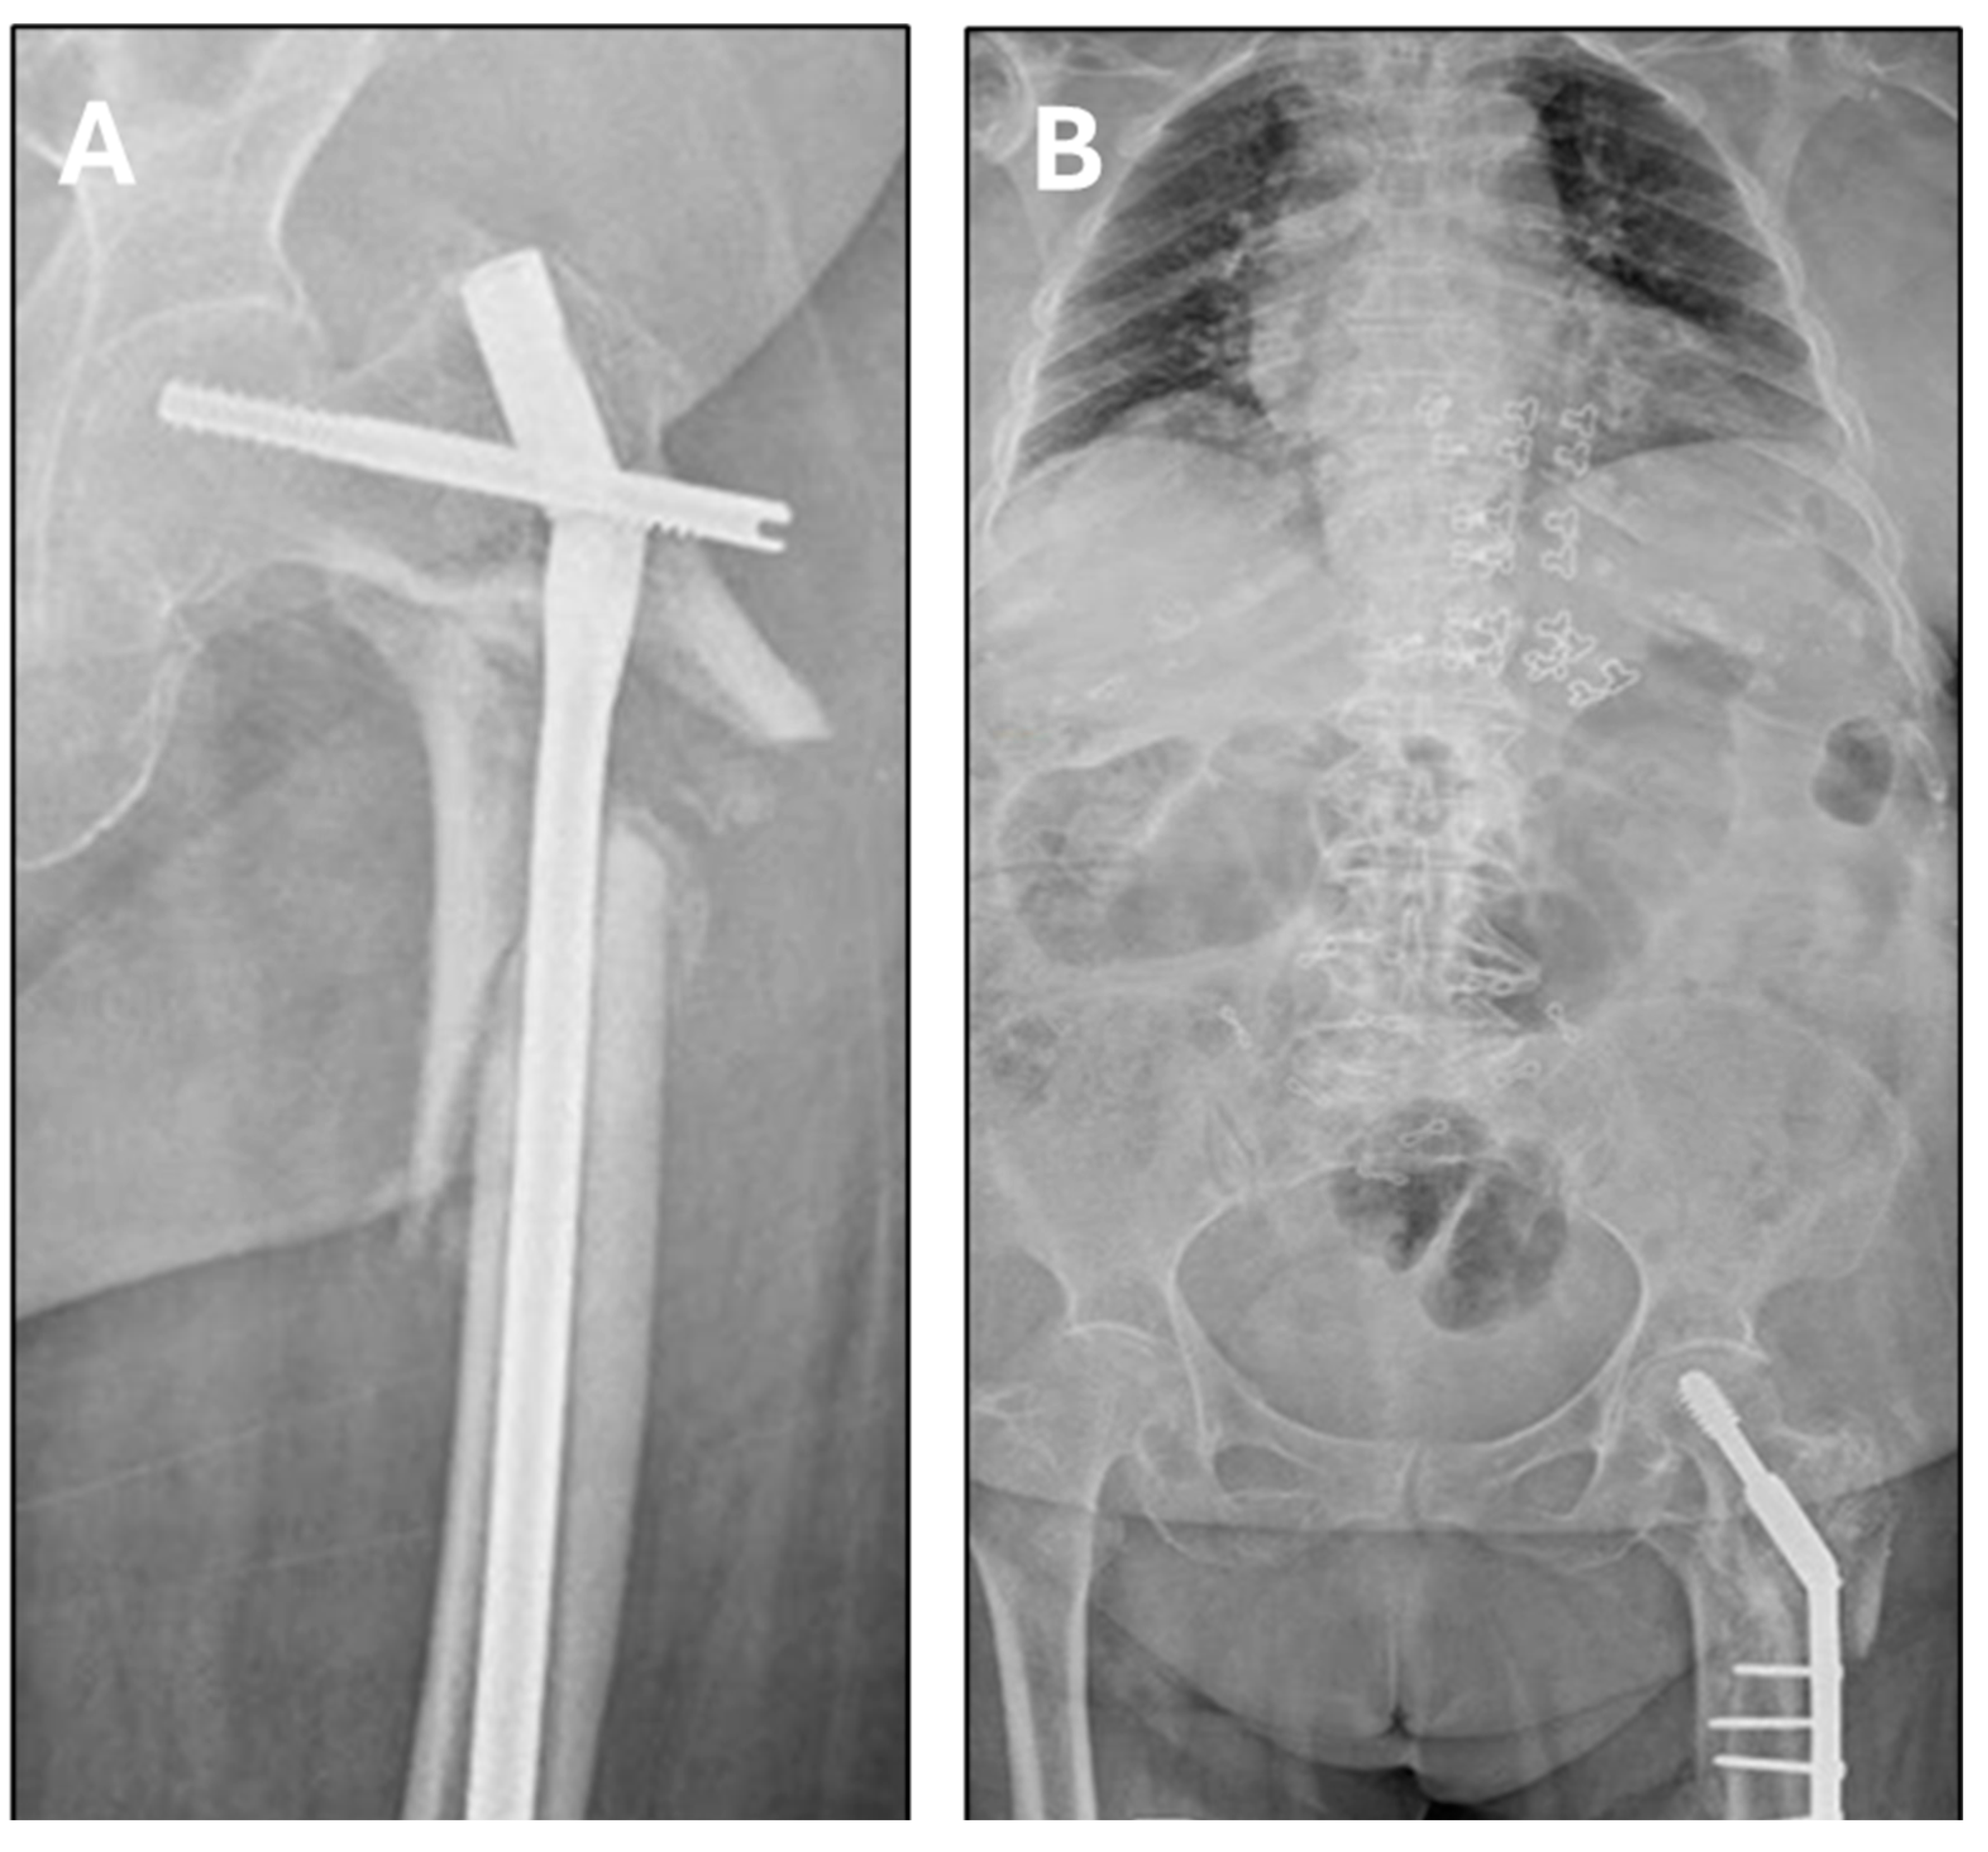

5. Surgical Procedure